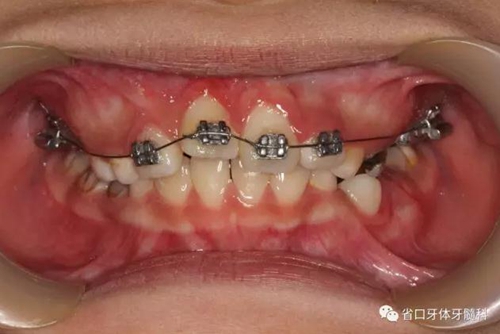

局部固定矯治器進(jìn)一步牽引、排齊11

6個(gè)月后11牽引到位